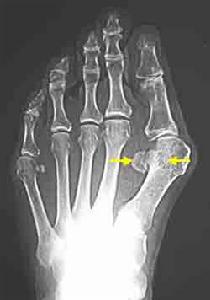

3.關節病變與變形性骨炎相伴的關節病變有關節畸形、退行性關節病變、軟骨鈣鹽沉積和假性痛風、鈣化性關節周圍炎等。骨病變畸形可能導致關節畸形,但變形性骨炎本身很少侵犯關節軟骨面;當骨畸形累及髖關節相鄰部位時,因運動應力異常可導致關節異常磨損軟骨缺損,而下層出現假血管瘤樣物晚期出現髖臼內陷。膝關節也有類似情況。在遠離病灶的部位,可出現鈣化與病變的擴展無關。

X線的表現較複雜可歸納為下列數點:①骨質破壞骨小梁粗糙稀疏伴局限性骨質疏鬆晚期的骨皮質與髓質腔界限不清,結構模糊如網狀;②骨幹增粗,膨大,彎曲變形,呈腰刀狀;③顱骨局限性骨質疏鬆伴棉絮狀增生,內外板界限消失,顱縫模糊,頭顱增大;④椎體呈柵欄狀和方框狀改變;⑤長骨溶骨性病灶有時呈V形;⑥骨盆連緣和弓狀線增厚,出現邊緣征;⑦髖關節間隙變窄,骨質增生短骨增粗;⑧病變區病理性骨折。